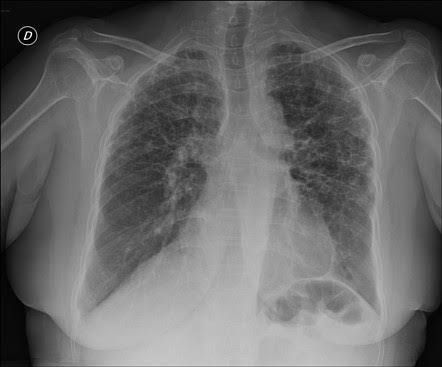

Williams–Campbell syndrome (WCS) is a disease of the airways where cartilage in the bronchi is defective. It is a form of congenital cystic bronchiectasis. This leads to collapse of the airways and bronchiectasis. It acts as one of the differential to allergic bronchopulmonary aspergillosis.